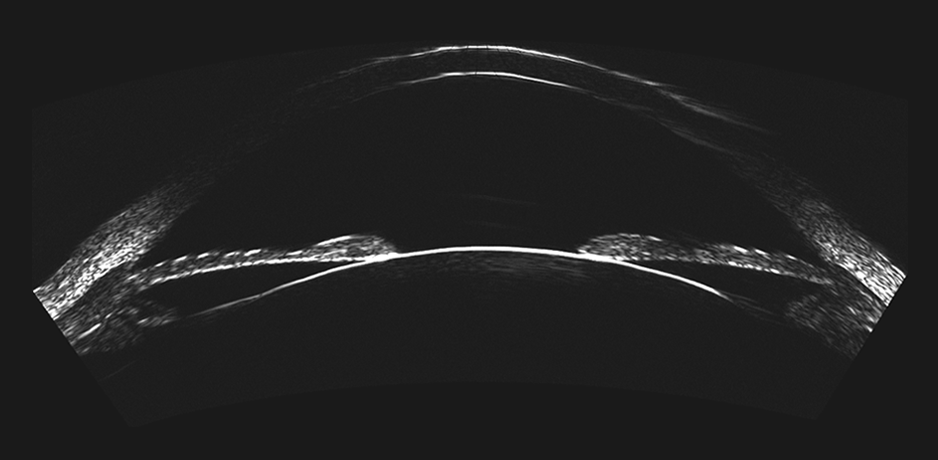

The ArcScan Insight® 100 is an intelligent anterior segment imaging system that uses very high frequency ultrasound technology. The ArcScan Insight® 100 device and software create a powerful platform that enables users to easily obtain stunning high resolution images in micron precision of the entire anterior segment, including areas that can not be imaged with optical technologies.

Wide-angle cornea layer mapping for keratoconus screening and inlay evaluations.